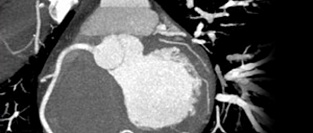

Сахарный диабет и скрининговая КТ-ангиография коронарных артерий. Обосновано ли использование?

Скрининг в отношении бессимптомного обструктивного атеросклероза коронарных артерий у пациентов с са...

15.12.2014 6419 #сахарный диабет #сахарный диабет 2 типа #КТ-ангиография